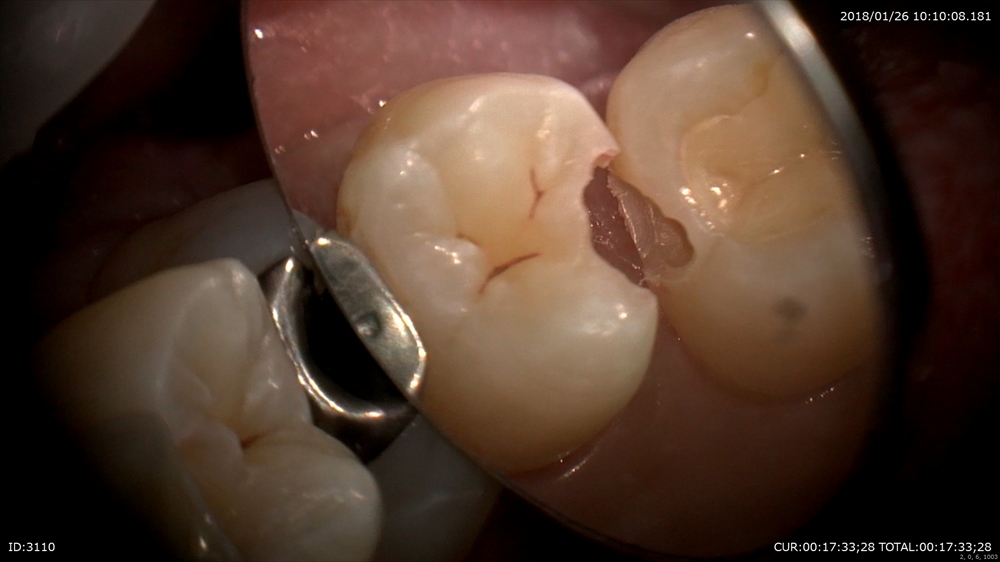

むし歯治療 穴があいていますね。

むし歯は大体中で広がります。 検知液で確認